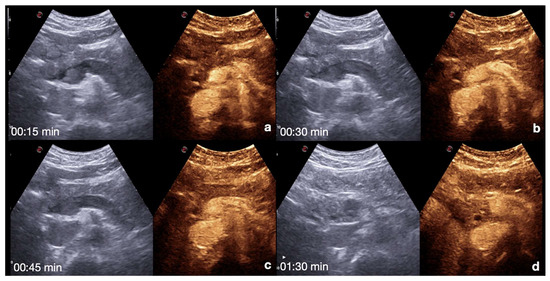

Spleen: the arterial phase starts 12–20 s after the injection. This phase shows irregular enhancement, similar to what is seen during MDCT, making it difficult to define any parenchymal injury. The venous phase starts 40–60 s after the injection. This phase provides adequate organ injury detection as the healthy parenchyma appears with a homogeneous enhancement for 5–7 min (Figure 7) [13,26,30].

Figure 7.

CEUS findings in a normal spleen (a–d). Note the progressive physiological enhancement after contrast medium injection. Adopted from ref. [30], 2021, Iacobellis, F.; et al.